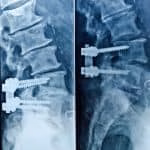

- Artrodese lombar

- ALIF, OLIF, TLIF